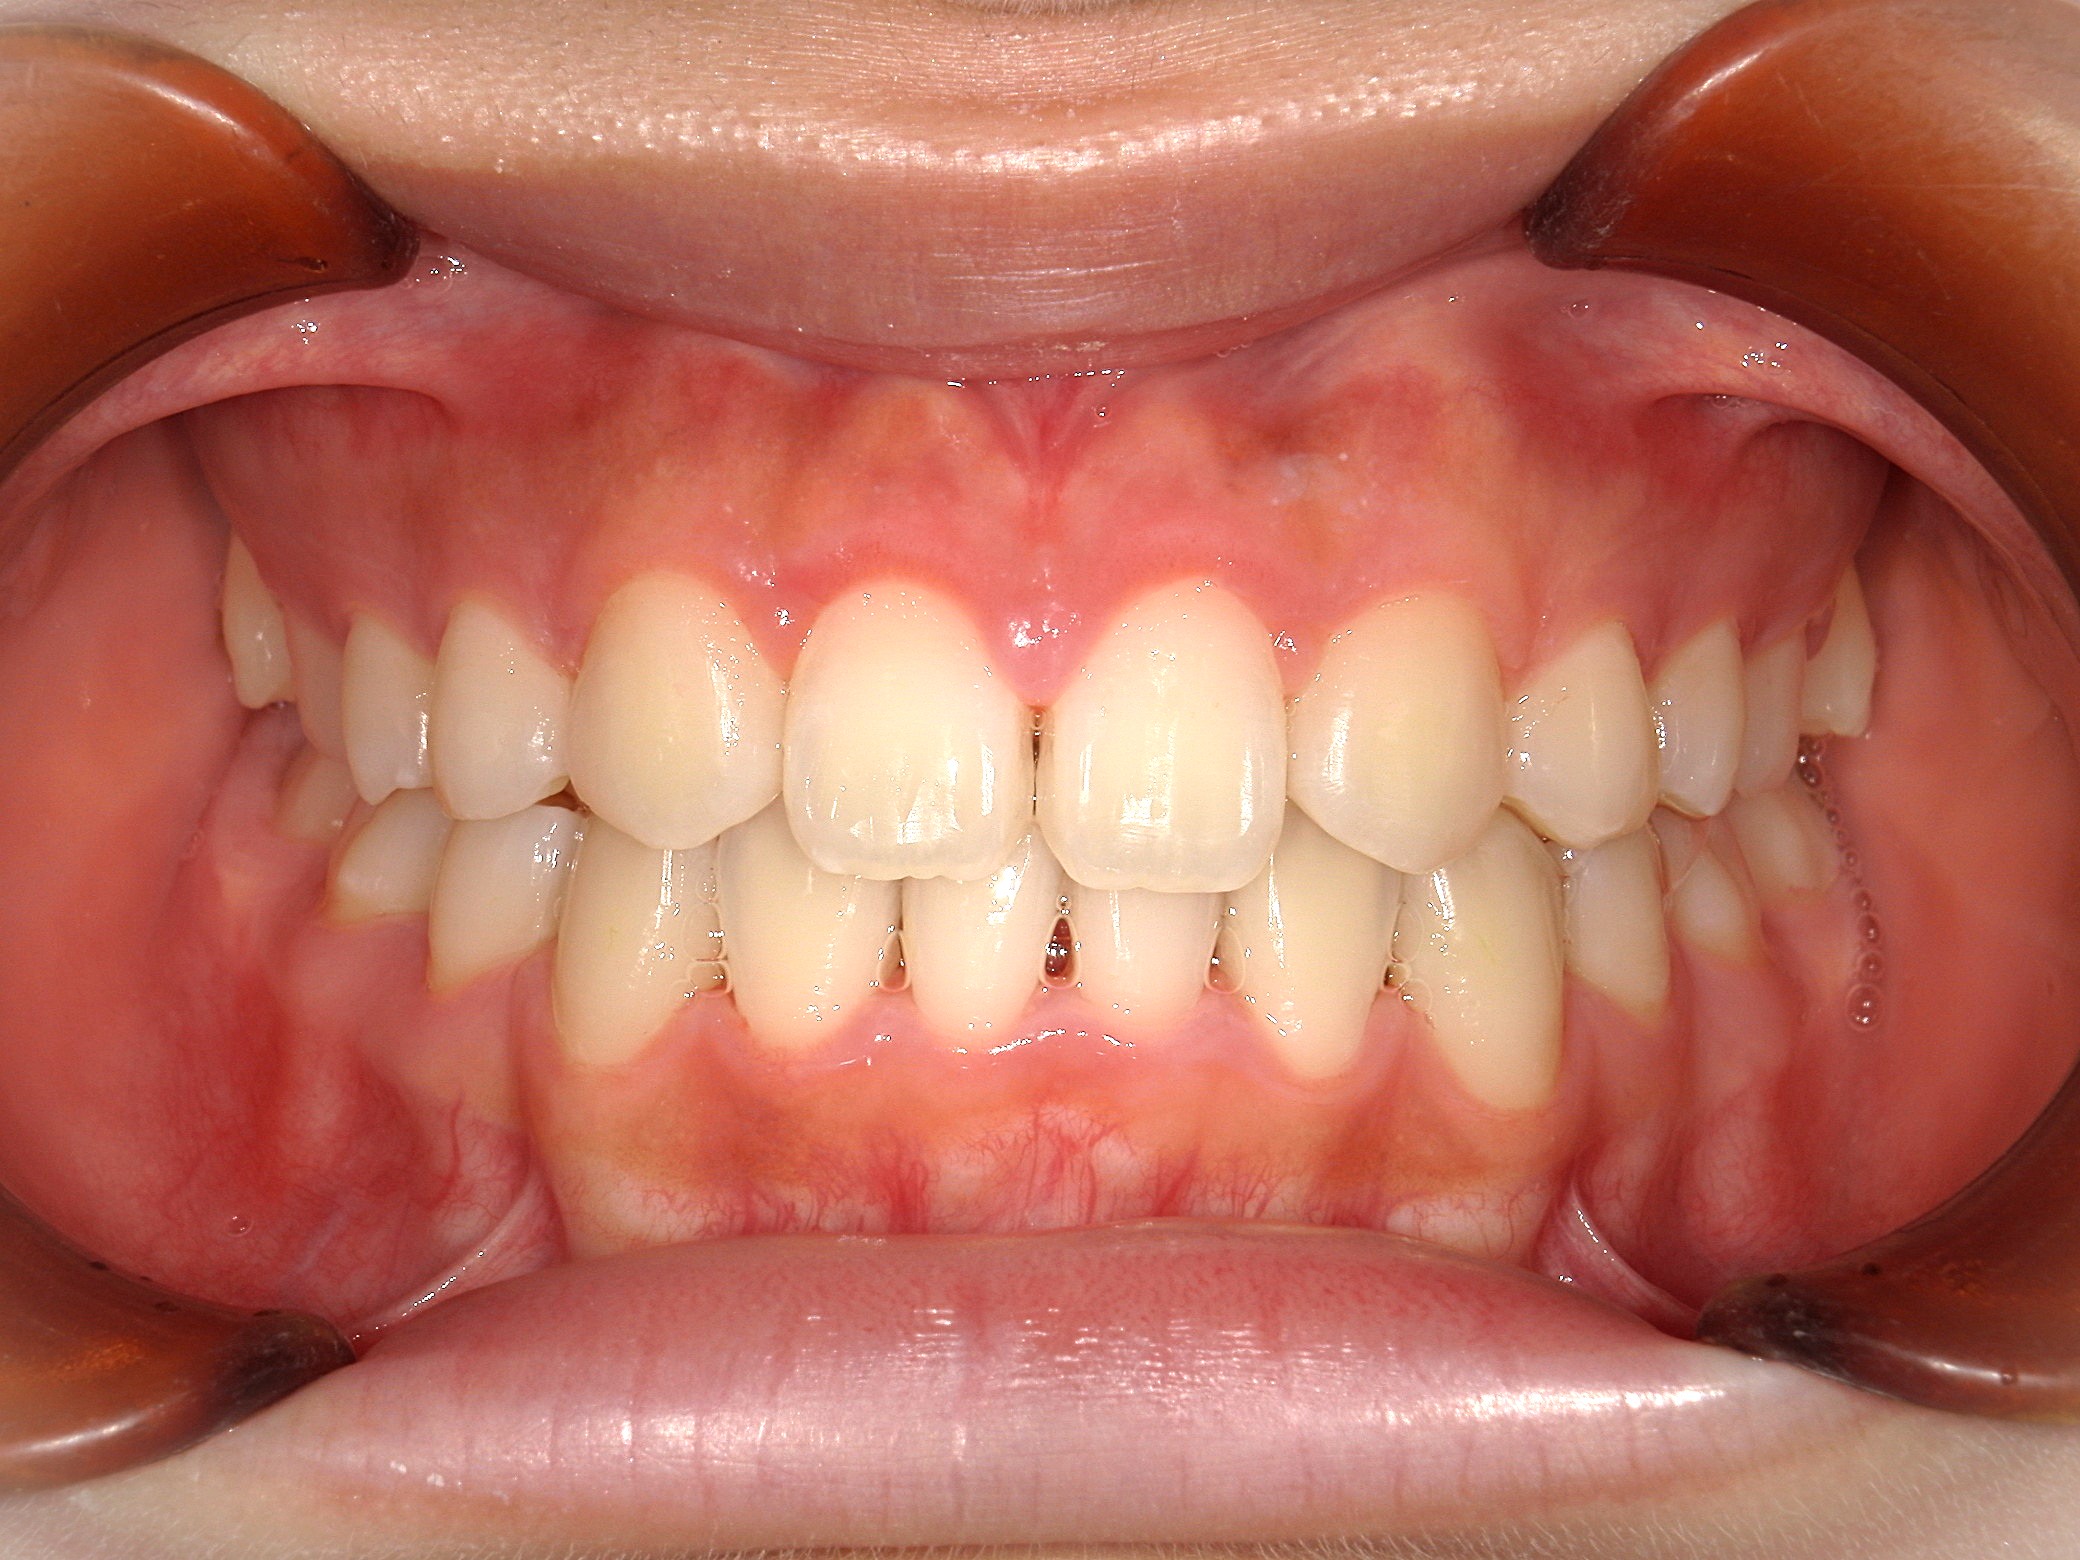

口内正面

治療前

上下の歯並びに凹凸があり、前歯の咬み合わせが深い状態でした。

また、上の前歯が2本、矮小歯(他の歯に比べて大きさが極端に小さい歯)でした。